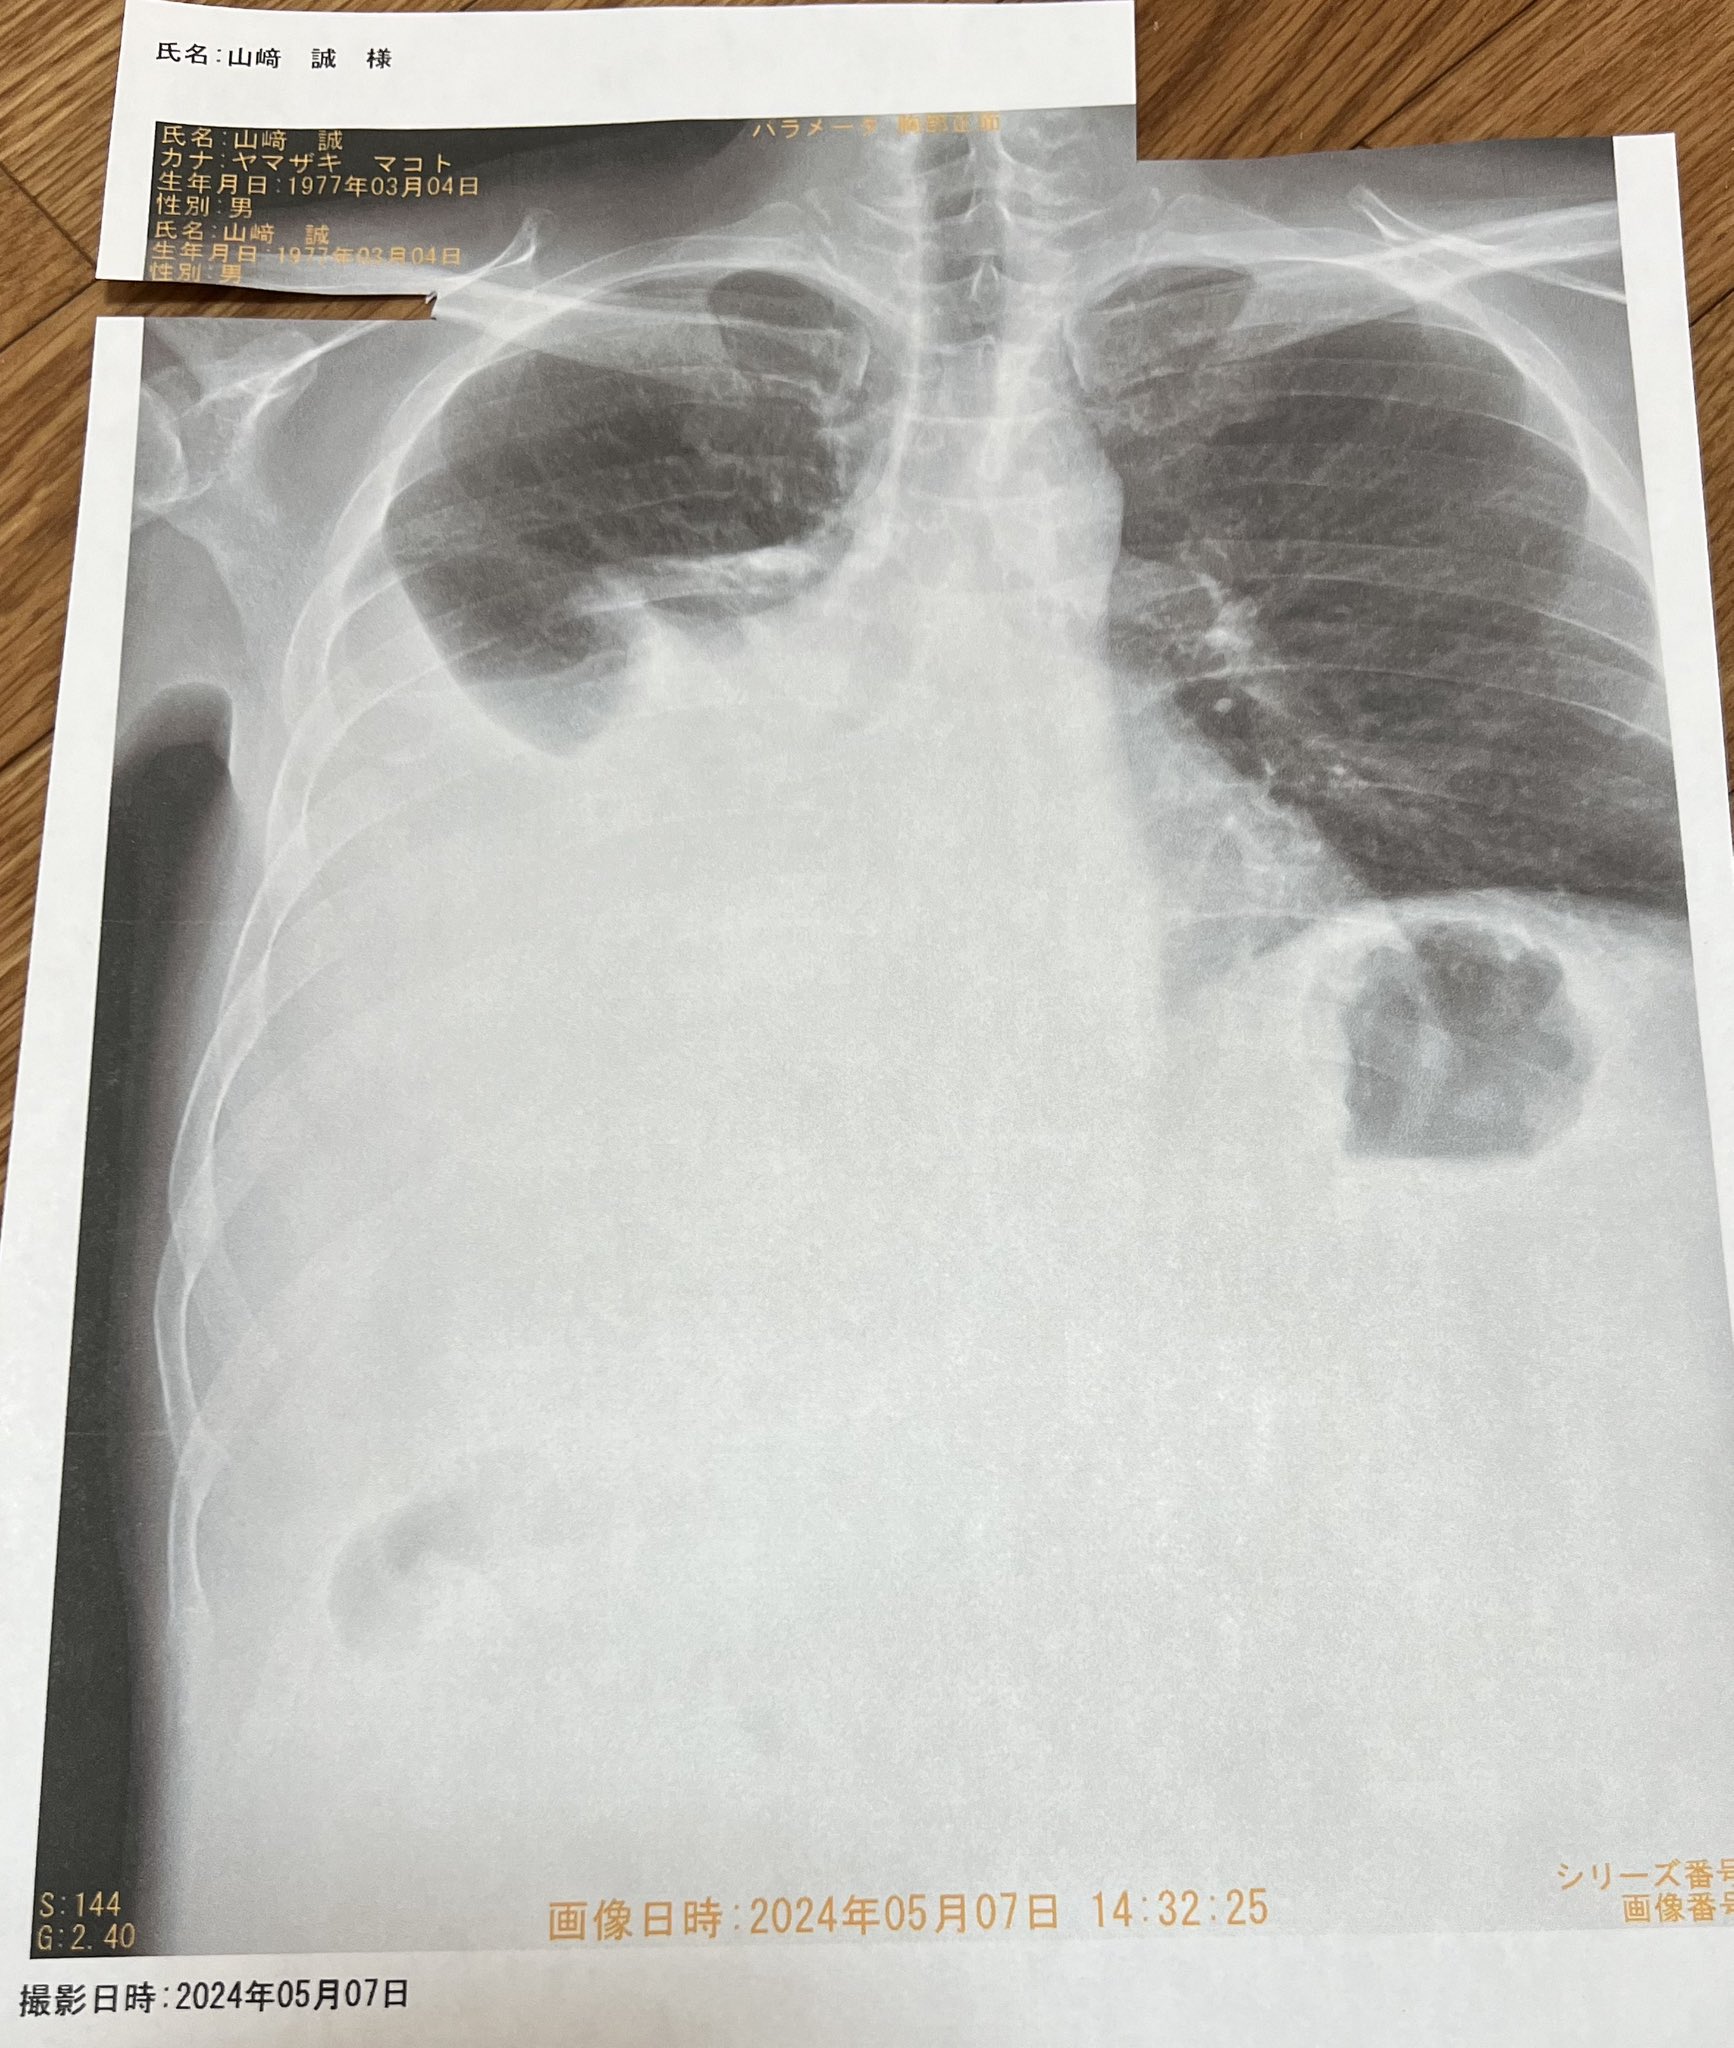

昨日のレントゲン写真です

白い部分が胸水

右の肺の3分の2が水溜まり

微妙に息苦しい

肺に針刺すの怖いなぁ

自然と抜けてくれないかなぁ